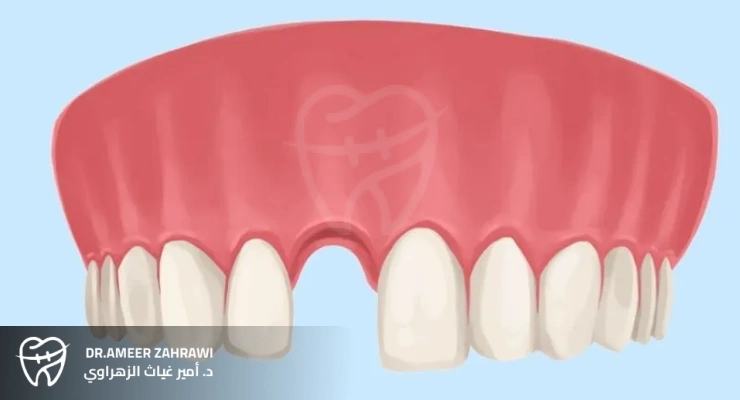

Front tooth restoration is a transformative dental procedure that not only replaces missing teeth, but also significantly enhances a person’s smile and overall self-confidence. Whether a tooth has been lost due to trauma, decay, or other reasons, restoring the front teeth is crucial for both cosmetic and functional reasons.With advances in modern dentistry, patients now have several options for replacing front teeth, including dental implants, bridges, and dentures. Each option offers unique benefits in terms of durability, natural appearance, and long-term oral health. By addressing a missing front tooth promptly, individuals can regain their ability to eat, speak, and smile comfortably, ultimately improving their quality of life and self-esteem.

When it comes to replacing missing front teeth, there are several front tooth restoration options available, each with its own advantages and considerations: